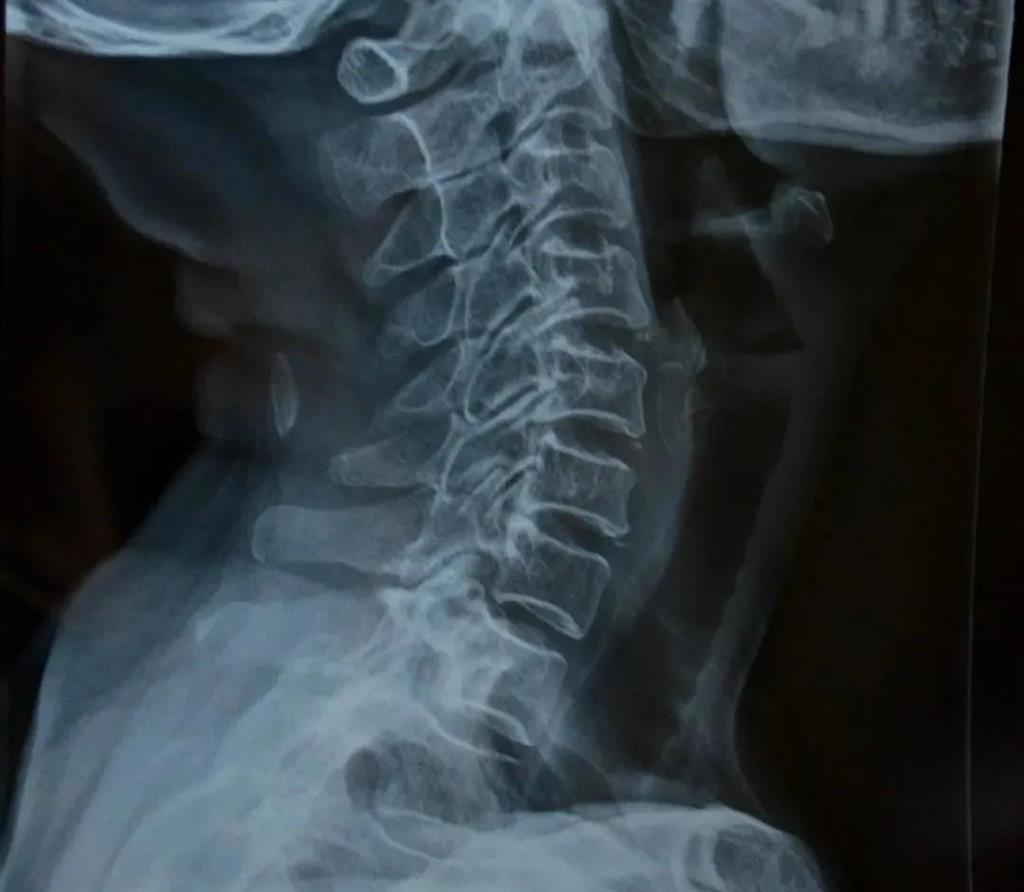

X光片檢查

——圖源網絡

可得信息:

(1)判斷頸椎的大體形態、曲度、穩定性;

(2)判斷骨頭結構是否出現破壞的情況;

(3)是否出現骨質增生或先天畸形的情況。